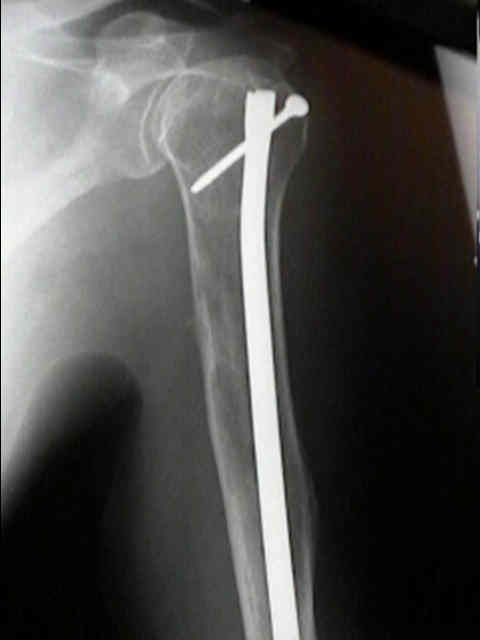

Surgical Fixation

- Treatment of pathologic fracture of the humerus.